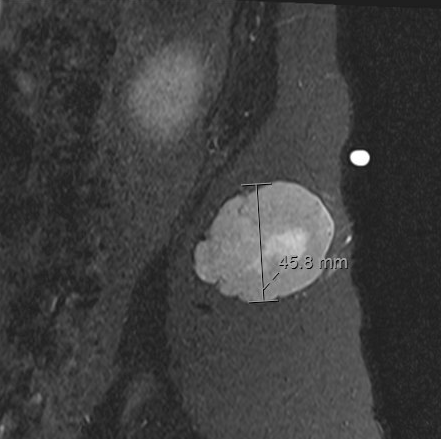

- • The work-up often consists of a physical examination, X-rays, CT scans, MRI, and sometimes bone scans are required.

- • MRI is the best imaging because it is the most sensitive.

Radiographic imaging is used to help form a diagnosis. These include X-Ray, MRI, CT and Bone Scans.

An example of a MRI is shown.